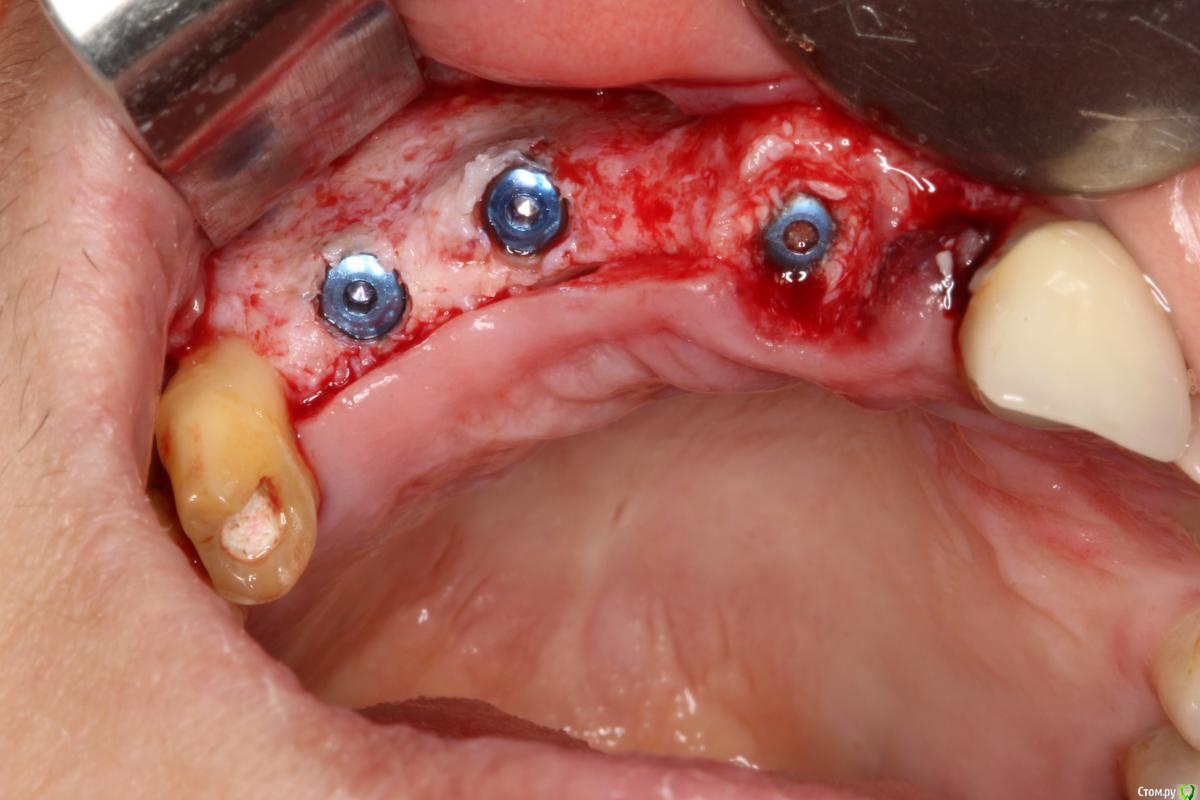

Robinbobin Опубликовано 9 сентября, 2015 Поделиться Опубликовано 9 сентября, 2015 Зуб 1.1 удалил,кюретаж и одномоментно установлен имплантат, заполнил MP3 и закрутил заглушкуУстановил имплантаты в области 1.3,1.4 подсыпал так же MP3 под мембрану и запинилЕсли покажите пальцем на ошибки буду благодарен))) 4 Ссылка на комментарий

колесников Опубликовано 9 сентября, 2015 Поделиться Опубликовано 9 сентября, 2015 Одномоментно желательно глубже ставить ,до 2мм по гребню уходит в последствии. У 12 обязательно сст . Впрочем можно было и в обл 13,14 им обойтись,но это дело вкуса. П-образный шов препочтителен,не будет расхождений и дополнительный объем на вершине получается. Ссылка на комментарий

zzkz Опубликовано 10 сентября, 2015 Поделиться Опубликовано 10 сентября, 2015 кмк можно ССТ положить и не аугментироваться в обл 13,14 Ссылка на комментарий